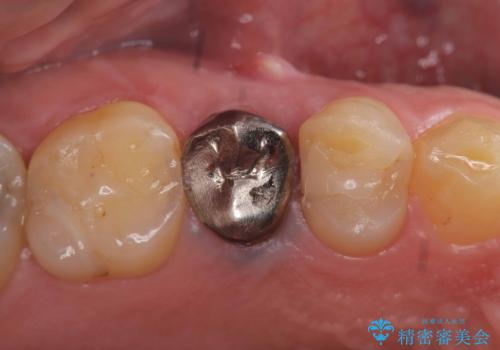

セラッミクインレー|オールセラミッククラウン|銀歯による二次カリエス|ラバーダムシート使用

銀歯の下の虫歯|オールセラミッククラウン|歯を長持ちさせるための治療|歯の神経を守る